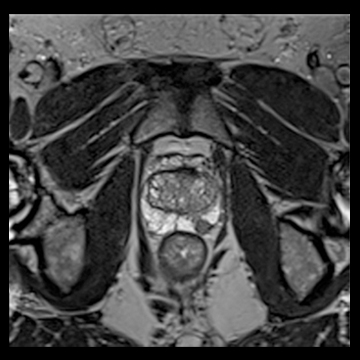

前立腺

高分解能T2

T2

RESOLVE, b=800

and ADC map,